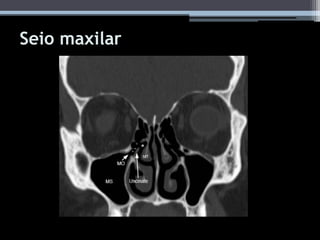

Seio maxilar

• #34 Coronal image with arrowhead pointing to infraorbital ethmoid air cell ( Haller cell) which is narrowing the maxillary sinus ostium and infundibulum. (MT: middle turbinate, MS: maxillary sinus. EM 45 % DA POPULAÇÃO.